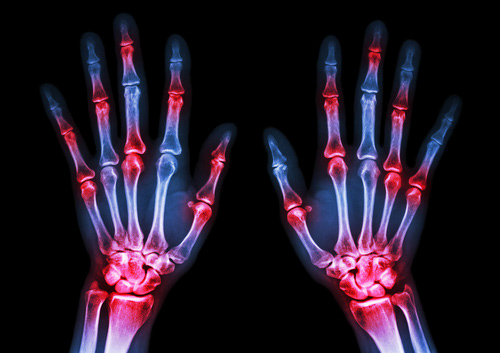

A recent surge in computer vision research has produced a standout breakthrough: an AI system that fully automates the scoring of rheumatoid arthritis from X-ray images with accuracy rivaling human radiologists[1]. Published among 80 computer vision papers on September 8, 2025, this innovation signals a major advance for medical diagnostics both in speed and reliability.

Rheumatoid arthritis (RA) is a chronic disease often requiring frequent imaging for effective management. Traditional RA scoring is labor-intensive and prone to inter-expert variation, leading to delays and inconsistent care. The new AI model leverages advanced vision architectures to analyze X-rays and generate scores instantly, streamlining workflow and standardizing results[1].

- Fully automated: The system can process standard X-ray inputs, deliver a diagnostic score, and present annotated findings with no human intervention required.

- Expert-level accuracy: Benchmarking shows its performance matches or exceeds experienced medical professionals, especially in identifying subtle disease progressions[1].